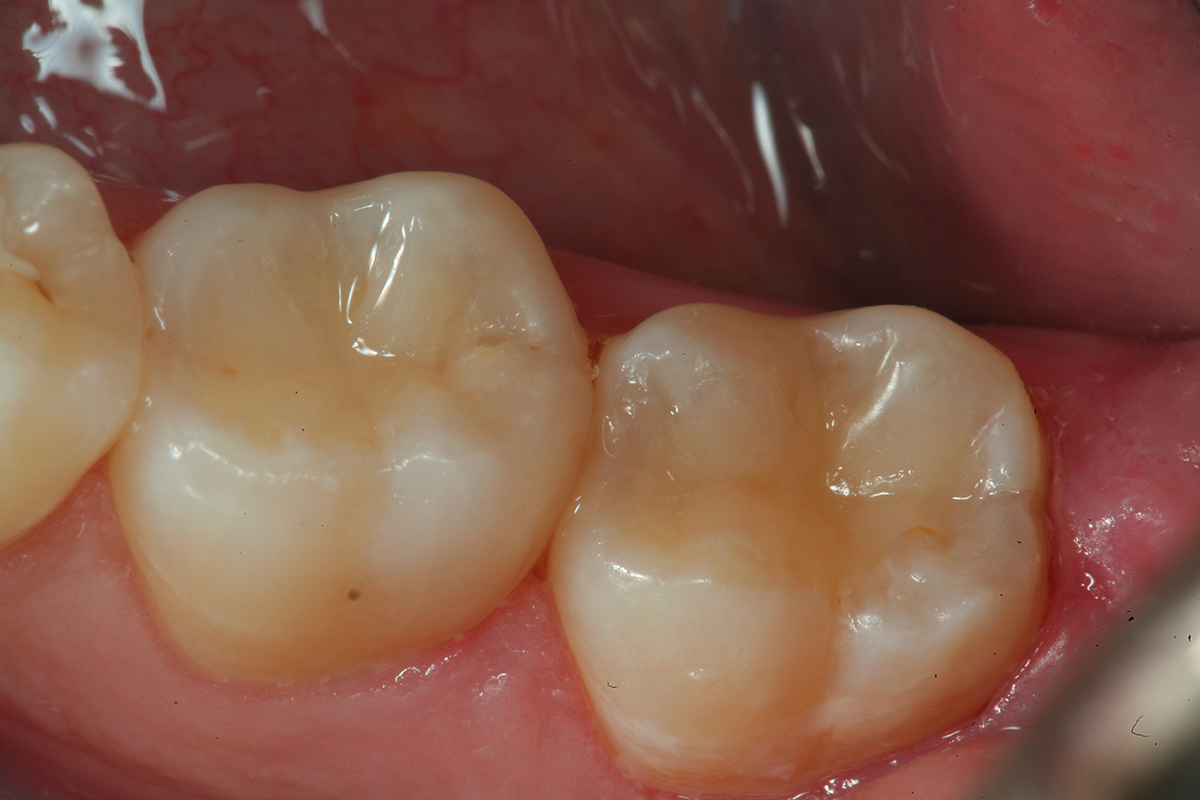

Fig 14. An occlusal view of the completed composite restorations on teeth Nos. 18 and 19.

Figure 14